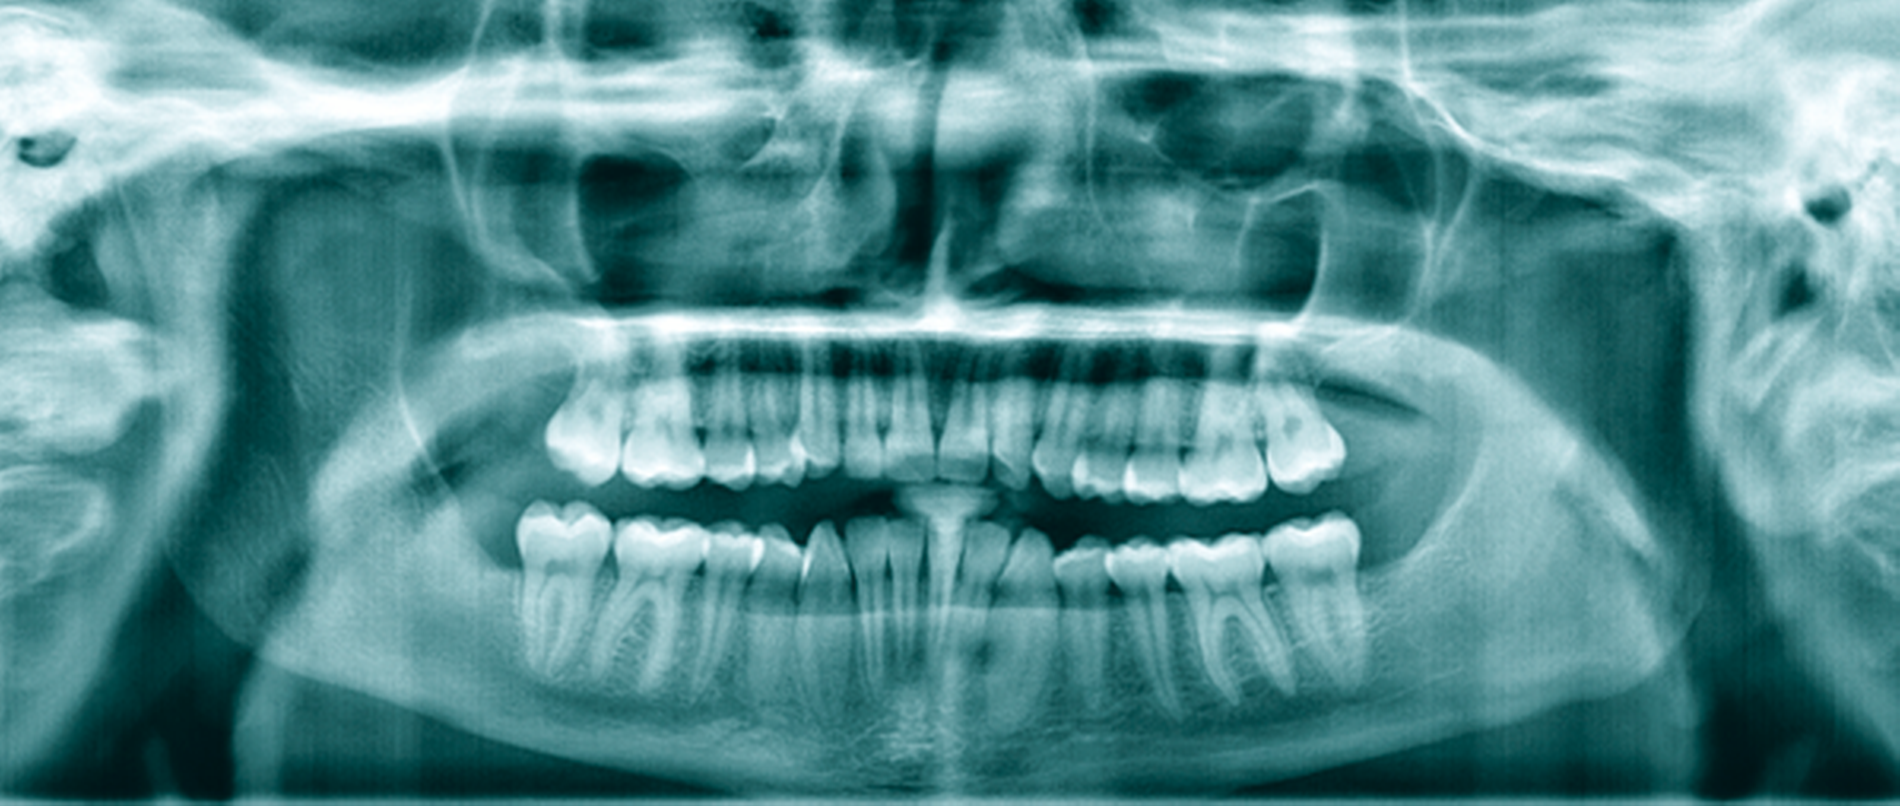

Eine 72-jährige Patientin wurde zur Therapie einer Zyste in regio 48 in unser MVZ überwiesen. Es handelte sich um einen Zufallsbefund im OPTG. Klinische Beschwerden wurden von der Patientin verneint (Abbildung 2a). Vorerkrankungen bestanden abgesehen von Migräne nicht. Zur Beurteilung der Zystenausdehnung erfolgte eine Computertomografie des Gesichtsschädels, die insbesondere eine basal stark ausgedünnte Kortikalis zeigte. Nach Erörterung der therapeutischen Möglichkeiten entschied sich die Patientin für eine Zystostomie, da die Zystektomie mit einem erheblichen Frakturrisiko, der möglichen Schädigung des N. alveolaris inferior sowie einer Behandlung in Allgemeinanästhesie verbunden gewesen wäre. In Lokalanästhesie wurde über einen marginalen Zugang in regio 47-48 eine Biopsie des Zystenbalgs gewonnen sowie eine Drainage ins Zystenlumen inseriert. Histologisch konnte eine follikuläre Zyste gesichert werden.

Die täglichen Spülungen des Lumens über die einliegende Drainage mit NaCl-Lösung erfolgten durch die Patientin selbst nach entsprechender Instruktion. Dies führte sie für sechs Monate selbstständig durch. Zwischenzeitlich musste das Drainageröhrchen wegen Verlusts erneut inseriert werden. Im DVT zeigte sich nach sechs Monaten eine signifikante Ossifikation am Rande des Zystenlumens und der N. alveolaris inferior wies wieder eine knöcherne Ummantelung auf (Abbildung 2b). Somit konnten die Zystektomie des verbliebenen Befunds und die Entfernung von 48 in ITN erfolgen. Dabei und postoperativ traten keine Komplikationen auf. Zahn 47 ist unverändert vital. Die extrem verlagerten Zähne 18 und 28 wurden auf Wunsch der Patientin belassen. Nach vier Monaten stellt sich im OPTG ein nahezu vollständig ossifizierter Defekt dar und die Patientin ist vollkommen beschwerdefrei (Abbildung 2c).